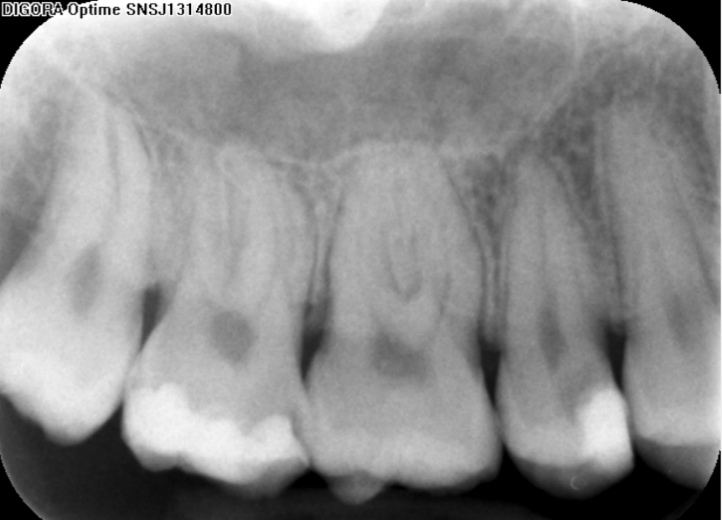

aprezentowany powyżej problem jest dość złożony. Podejmując się leczenia pierwszego zęba trzonowego u sześcioletniej osoby należy zdawać sobie sprawę z faktu, że korzenie zęba nie są w pełni ukształtowane i z całą pewnością kanał nie ma kształtu stożka zwężającego się w kierunku wierzchołka, ściany korzeniowe są cienkie, a otwory wierzchołkowe bardzo szerokie. Stąd należy zachować szczególną ostrożność podczas opracowywania głębokich ubytków w zębach z niezakończonym rozwojem i dążyć do zachowania żywej miazgi unikając tym samym bardzo trudnego do wykonania i nieprzewidywalnego leczenia endodontycznego. Ponieważ rozpoznano klinicznie próchnicę głęboką należało wykonać zdjęcie rentgenowskie i ocenić głębokość ubytku. Europejskie Towarzystwo Endodontyczne wyróżnia 2 typy próchnicy głębokiej, tj.: próchnicę głęboka (deep caries, ryc. 1) i próchnicę bardzo głęboką (extremely deep caries, ryc. 2). W przypadku próchnicy głębokiej na zdjęciu rentgenowskim widoczna jest warstwa zębiny oddzielająca dno ubytku od sklepienia komory o grubości 1/4 -1/3 szerokości (grubości całej zębiny) (ryc. 1 B), podczas gdy w próchnicy bardzo głębokiej proces próchnicowy niszczy zębinę na całej jej grubości (na zdjęciu nie widać zmineralizowanej warstwy zębiny oddzielającej dno ubytku od komory miazgi) (ryc. 2 B). W prezentowanym przypadku na pewno nie byłoby problemu z postawieniem diagnozy (głęboka vs. bardzo głęboka) ze względu na lokalizację ubytku na powierzchni zwarciowej (dobra widoczność ubytku zdjęciu rentgenowskim w związku z nienakładaniem się na niego zdrowych struktur, co z kolei ma miejsce np. w ubytkach klasy I zlokalizowanych na powierzchni policzkowej zębów trzonowych i tu trudno ustalić rozpoznanie na podstawie radiogramu). Ustalenie prawidłowego rozpoznania jest dość istotne, gdyż nieco inne jest postępowanie w przypadku, gdy mamy do czynienia z próchnicą głęboką niż gdy jest to próchnica bardzo głęboka. W obu przypadkach należy usunąć próchnicę ze ścian ubytku, natomiast z dna próchnicową zębiny należy usunąć selektywnie: w przypadku próchnicy głębokiej do tzw. zbitej zębiny, a w przypadku próchnicy bardzo głębokiej nawet pozostawiając na dnie miękką zębinę (w tabeli 1 dla przypomnienia typy zębin). W pierwszym przypadku postępowanie polega na zastosowaniu na dno (w tym na pozostawioną na dnie zdemineralizowaną zębinę) materiału bioaktywnego (najlepiej cementu krzemowo-wapniowego względnie c. szkło-jonomerowego lub preparatu wodorotlenkowo-wapniowego), a następnie po założeniu ew. podkładu na wypełnieniu ostatecznym ubytku (ryc. 3). W drugim przypadku, gdy pozostawiamy miękką zębinę ubytek należy wypełnić czasowo na 6-12 miesięcy (leczenie dwuetapowe). Dno, tak jak w pierwszym przypadku najlepiej szczelnie przykryć cementem bioaktywnym na bazie krzemianu wapnia (ryc. 4). Takie postępowanie w próchnicy głębokiej, czyli selektywne usunięcie próchnicowej zębiny dokomorowej obarczone jest znacznie mniejszym ryzykiem powikłań ze strony miazgi aniżeli nieselektywne, czyli doszczętne usunięcie zębiny próchnicowej do zębiny twardej (zdrowej). Co więcej w przypadku próchnicy bardzo głębokiej próba usunięcia zębiny próchnicowej nawet do tzw. zębiny zbitej skutkuje odsłonięciem miazgi. W przypadku dwuetapowego leczenia próchnicy należy po upływie określonego czasu (6-12 miesięcy, a w przypadku zębów niedojrzałych najbezpieczniej do momentu zakończenia rozwoju korzenia) usunąć wypełnienie czasowe i sprawdzić, czy miękka zębina uległa mineralizacji. Jeśli zębina uległa mineralizacji, to nie ma potrzeby tzw. „doczyszczenia” ubytku, choć w wielu przypadkach okazuje się konieczna dodatkowa preparacja.

Ryc. 1. Próchnica głęboka. A. Schemat, B. Zdjęcie rentgenowskie